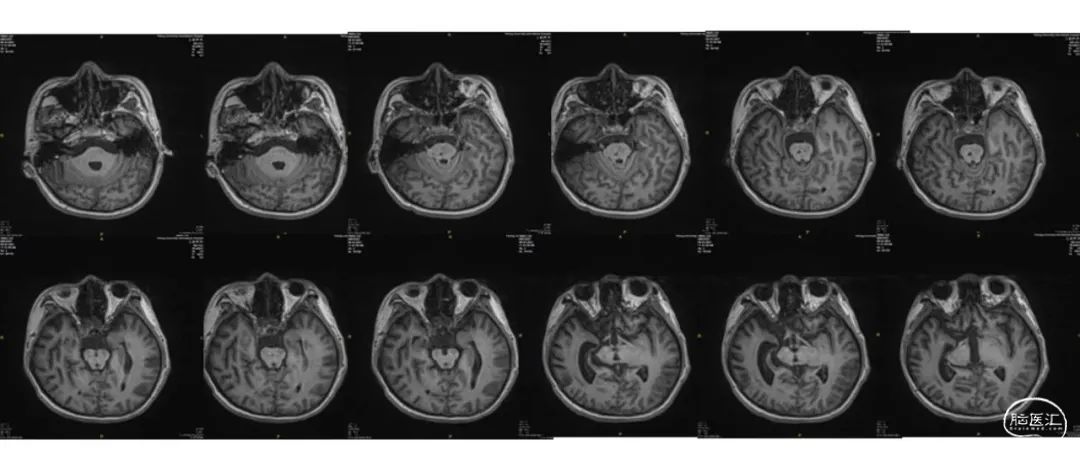

在患者的基本状态好转之后,进一步进行了意识水平相关的系列检查。核磁共振,显示脑干有局灶损伤,但是全脑皮层结构完好,清醒的概率很大。